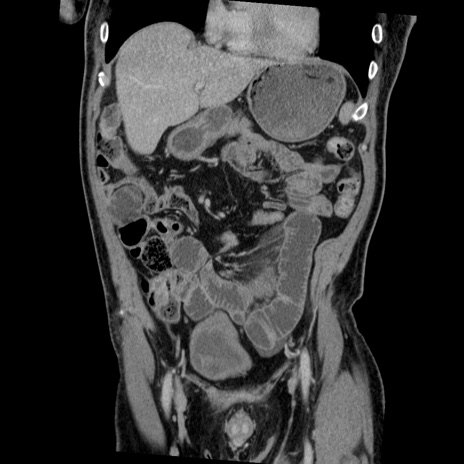

症例22(冠状断像)

【症例】50歳代男性

【主訴】腹痛

【現病歴】AVMからの被殻出血のため回復期リハ病棟入院中。 本日午後3時頃急に下腹部痛が出現した。

【既往歴】AVM、被殻出血、虫垂炎、高血圧

【身体所見】意識晴明、左半身不全麻痺、会話の理解は良好、36.5°C、腹部:膨隆、全体に板状硬、下腹部正中に圧痛点あり、反跳痛-、筋性防御不明、右下腹部にope scar

【データ】WBC 9400、CRP 0.06

横断像